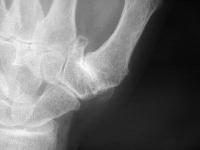

Advanced degenerative changes of the joint: loss of joint space, subchondral sclerosis, large osteophyte, erosions, all with preservation of the adjacent joints.